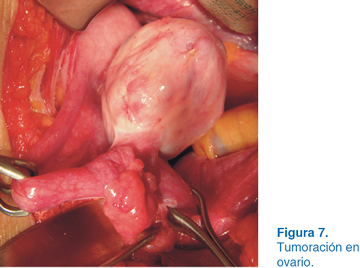

Se realizó laparotomía exploradora con abordaje a través de incisión en la línea media, se encontró tumoración en ovario izquierdo (Figura 7) y se hizo una incisión en la tumoración (Figura 8) hasta realizar salvamento de tejido ovárico (Figura 9) y visión final (Figura 10). El reporte histopatológico fue de teratoma maduro de ovario, con bordes libres de neoplasia. La evolución postoperatoria fue satisfactoria.